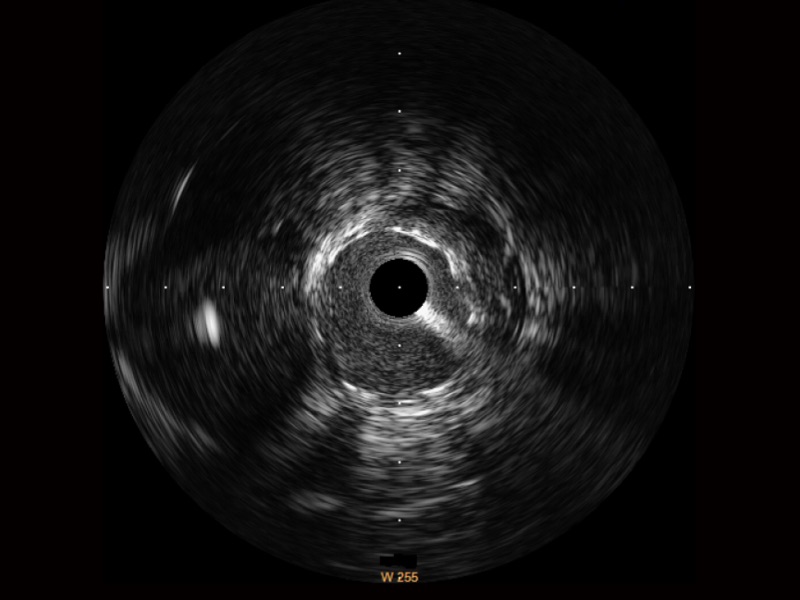

傳統(tǒng)IVUS圖像

對(duì)比傳統(tǒng)IVUS導(dǎo)管成像,開(kāi)立寬頻IVUS圖像的近場(chǎng)支架梁顯影更細(xì)膩,遠(yuǎn)場(chǎng)中膜外血管仍清晰可辨,兼顧遠(yuǎn)中近,兼顧分辨力與穿透深度